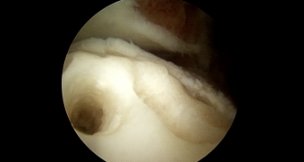

발목 연골 손상은 발목 염좌나 골절 등 여러 가지 원인에 의해 관절에 염증이 생기는 질환입니다. 발목 연골 손상이 발생할 시 지속된 통증과 불편감과 붓기가 발생하고 발목의 불안정성이 같이 동반되어 있는 경우가 종종 있습니다. 발목 연골 손상의 치료법 중 하나인 발목 연골 자가골수 줄기세포 치료(BMAC)는 환자 본인의 엉덩이뼈 및 골반뼈에서 뽑은 골수액에서 줄기세포를 채취해 연골이 결손된 부분에 넣어 회복시키는 수술입니다.

발목 연골 줄기세포 치료는 본인의 연골을 보존 및 재생할 수 있는 장점이 있으며, 연골 재생 성공률은 70-80%로 치료 효과가 높습니다. 본원은 족부 전문의 3명이 10여 년간 타 병원과 비교할 수 없는 많은 경험을 바탕으로 발목의 연골 손상 치료를 성공적으로 시행해오고 있습니다.

발목 연골 자가 골수 줄기세포 치료는 수술의 부담이 적은 최소침습

관절내시경으로 시행됩니다. 따라서 수술 후 통증이 경미하고,

절개 부위 창상 감염 위험이 적고, 내시경 카메라를 통해 복잡한 발의

해부학적 구조에도 세심한 수술이 가능하여 주변 신경/혈관 조직

손상 없이 안전하고, 빠른 회복이 가능합니다.

수술 전

발목 연골이 손상된 환자의 발

연골 손상부위 확인

BMAC 삽입 후

수술 후

발목 연골이 재생된 환자의 발